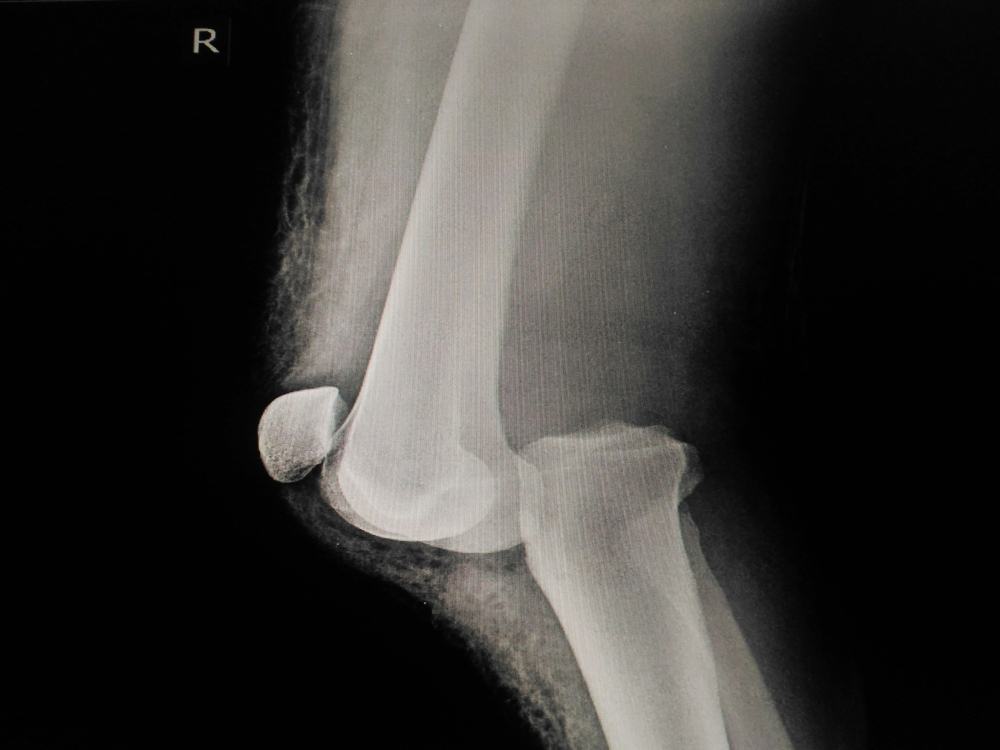

La lussazione del ginocchio (da non confondere con quella della rotula, che interessa quest’ultima e il femore) consiste nello spostamento della tibia, ossia la parte inferiore della gamba, rispetto al femore, cioè l’osso della coscia. E’ definita completa quando i capi ossei non hanno più nessun punto di contatto, e incompleta (o sublussazione) quando fra questi viene mantenuto un contatto parziale.

Se si sospetta una lussazione, è bene farsi visitare il prima possibile in un pronto soccorso: una volta confermata la diagnosi attraverso una radiografia. Il medico provvederà a riportare in sede i segmenti ossei mediante specifiche manovre dette di “riduzione”, per poi procedere a una risonanza magnetica (indispensabile per individuare eventuali danni ai tessuti molli che circondano l’articolazione).